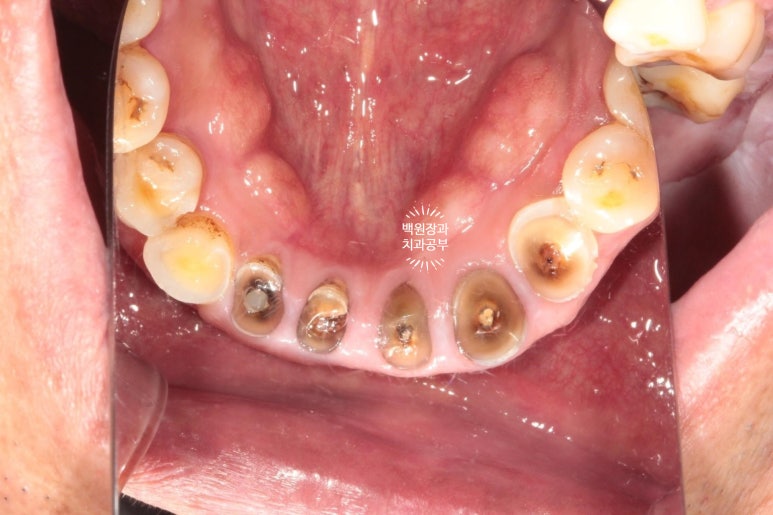

처음 오셨을 때의 상태입니다.

엑스레이를 같이 참고해 보셔야 하는데요,

양쪽 위 큰 어금니가 모두 발치된 상태로 오래 지내신 분이었어요.

보시면 상대적으로 아래 앞니가 머리가 매우 조금만 남아있는 것을 보실 수 있으실텐데요,

아래 앞니가 저렇게까지 극적으로 사라지게 된 경위를 살펴보자니

위 어금니가 없는채로 오래 지내시다보니

주로 앞니로 식사를 하게 됩니다.

위 앞니는 금속-도재 고정성보철물(PFM bridge)로 제작이 되어있는데요, 도재가 씌워진 보철물에 의해 아래 앞니의 마모가 가속화되고

결국 아래 앞니의 머리가 없어질때까지 깨지고 닳고.. 그런 과정을 거치게 된 것이죠.

대구치의 상실은 교합의 붕괴에 가장 큰 영향을 주는 것 같습니다.

아래 앞니의 마모도가 상당히 심합니다.

치과에서 교모(attrition)라고도 하는데요, 머리가 닳아 없어지다보니 치아 내부의 신경관이 드러나게 되고

그렇게 발생한 치통을 해결하기 위해 신경치료를 모두 받으셨던 흔적도 보여요.

여튼.. 심각합니다. 치료가 시급한 상태셨어요.